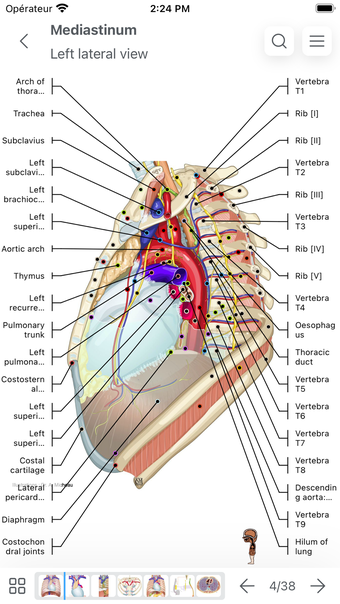

IMAIOS e-Anatomy es un atlas en línea de anatomía humana para médicos, enfermeras, estudiantes de medicina y técnicos en radiología. Utiliza IMAIOS e-Anatomy en tu smartphone o tablet para encontrar la ubicación de cualquier condición médica o estructura anatómica. El detallado e-Anatomy te proporcionará una referencia de acceso rápido de la anatomía humana y sus principales órganos y funciones.

Encuentra la ubicación de cualquier condición médica o estructura anatómica con IMAIOS e-Anatomy en tu smartphone o tablet. Busca enfermedades, anatomía y estructuras anatómicas, e incluso ve la ubicación de todos los puntos de referencia anatómicos. Puedes encontrar la ubicación de cualquier estructura o condición anatómica con la información médica detallada, fácilmente ingresando los detalles anatómicos relevantes.

Encuentra la ubicación de cualquier estructura o condición anatómica con IMAIOS e-Anatomy en tu smartphone o tablet. Utiliza la guía de anatomía para encontrar la ubicación de las estructuras anatómicas, enfermedades y trastornos, e incluso la anatomía y estructura de los dedos y manos.

IMAIOS e-Anatomy es un atlas médico. Utilízalo como referencia médica para averiguar dónde se encuentra cualquier condición médica o estructura anatómica en el cuerpo humano.

IMAIOS e-Anatomy es un atlas en línea de anatomía humana. Proporciona información médica detallada sobre la anatomía y estructura del cuerpo humano. Utiliza IMAIOS e-Anatomy en tu smartphone o tablet para encontrar la ubicación de cualquier estructura o condición anatómica.